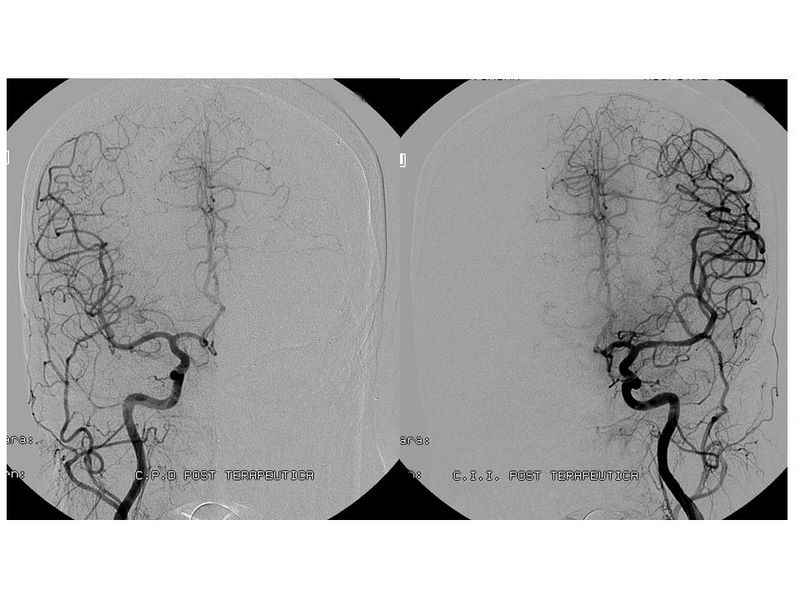

Ictus con stent